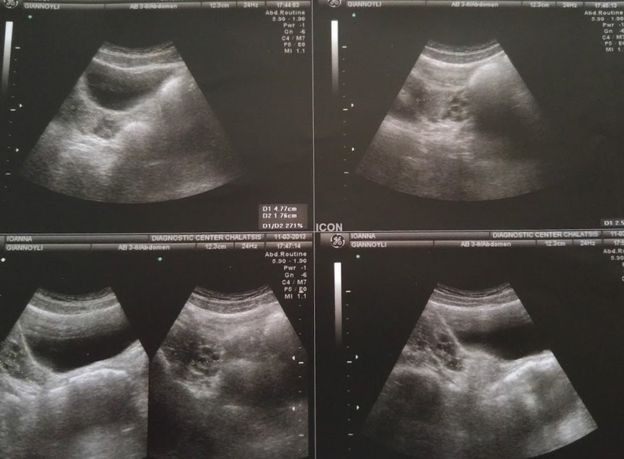

Pemeriksaan pertamanya tersebut mendapatkan dirinya didiagnosis menderita sindrom Rokitansky. Sindrom Rokitansky adalah kelainan genetik di mana seorang gadis lahir dengan alat kelamin eksternal yang normal, payudara dan rambut kemaluan, tetapi tanpa vagina, rahim atau serviks. Syndrom ini merupakan kondisi langka yaitu dengan perbandingan 1:4.500 anak perempuan.

Setelah mengetahui hal ini, Joanna dan keluarga pun segera berdiskusi dengan dokter setempat dan melakukan berbagai tindakan. Joanna harus mendapat operasi untuk membuat lorong vagina. Operasi tersebut dilakukan saat dirinya berusia 17 tahun. Paling tidak, Joanna harus berbaring selama 3 bulan penuh di rumah sakit setelah mendapat tindakan operasi.